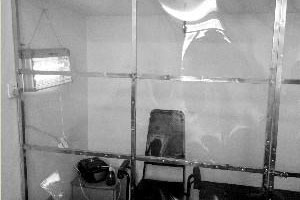

A 22-year-old college graduate, Chen Yang, suffers from uremia and can not afford the costly medical treatment, so he has to receive PD (peritoneal dialysis) treatment on his own. The young man spent1,800 yuan to build a sterile chamber in his home that is less than 3 meters square, roughly 2 meters long and 1 meter wide

After Chen fell ill, his father has bourne all the cost of supporting their family as his mother has to take care of him at home.(Modern Express)